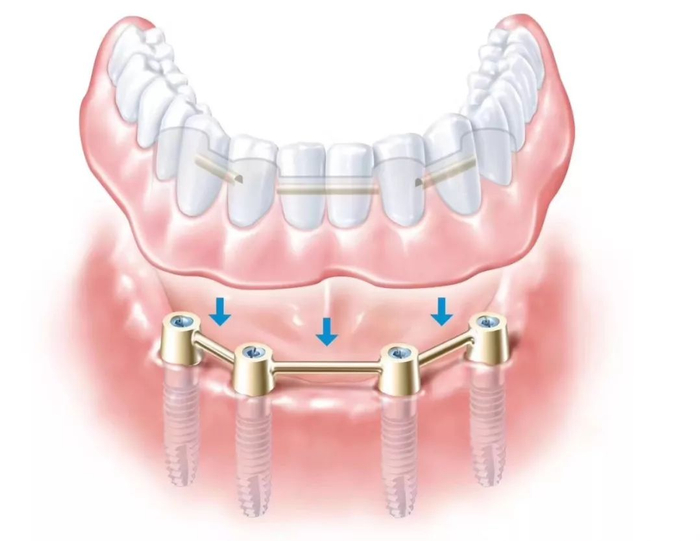

种植牙是医学界公认的理想修复方式,被誉为“人类的第三副牙”。相比活动假牙不舒服、难清洗、容易引起口腔黏膜病变,种植牙更稳固耐用,舒适美观,咀嚼功能好,一次种植,终生受用。种植牙不仅是中老年人的专利,年轻人因意外、牙病等造成牙齿缺失,也能够通过种植牙进行修复治疗,重获美丽笑容。

(单颗种植示例)